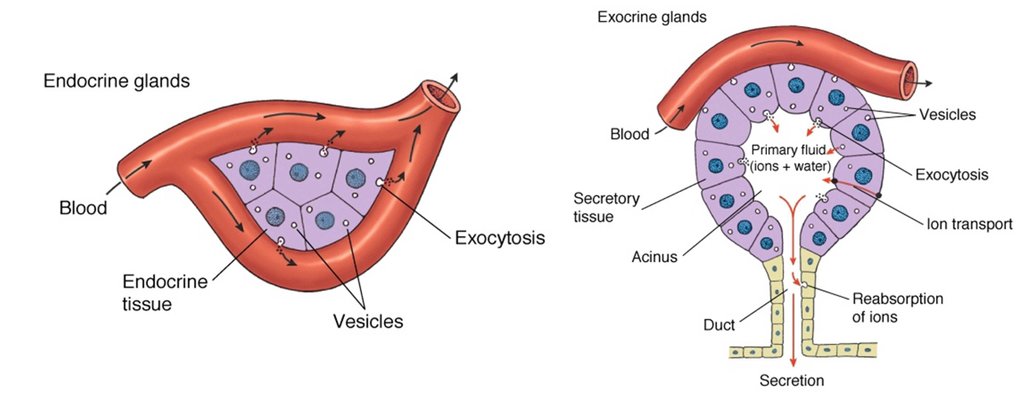

قیمت: 108٬000 تومان - دسته بندی فایل: علوم پزشکیپاورپوینت غدد درون ریز

فروش ویژه پاورپوینت حرفه ای غدد درون ریز با یک تخفیف استثنایی فقط 103134 هزارتومان تعداد اسلاید : 70 اسلاید

قیمت: 68٬000 تومان - دسته بندی فایل: علوم پزشکیپاورپوینت هورمون ها و دستگاه درون ریز

فروش ویژه پاورپوینت حرفه ای هورمون ها و دستگاه درون ریز با تخفیف استثنایی فقط 72400 تومان تعداد اسلاید: 32 اسلاید